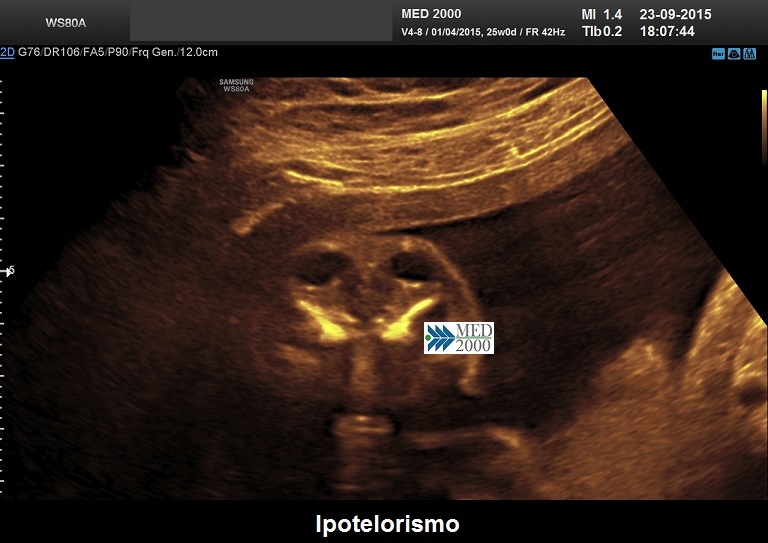

•    ipotelorismo

1. ciclopia: fusione parziale o totale dei globi oculari con naso a proboscide e narice unica

2. etmocefalia: ipotelorismo con microftalmia, naso a proboscide, narice unica

3. cebocefalia: ipotelorismo, naso piatto con narice unica

4. agenesia premascellare: ipotelorismo e labiopalatoschisi per agenesia della premascella